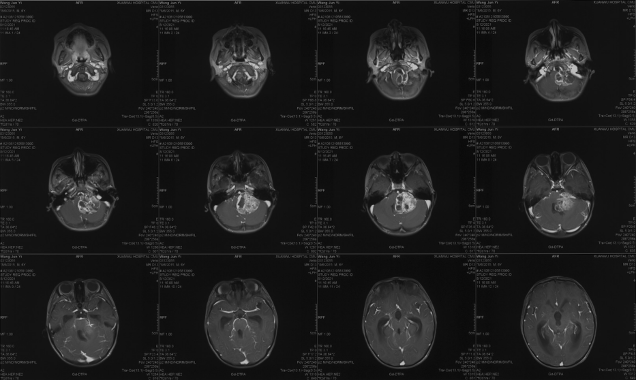

Pre-operative imaging

Preoperative imaging MRI-T2

Preoperative imaging MRI-T1

Preoperative MRI-DWI

Preoperative CT

Preoperative enhanced MRI